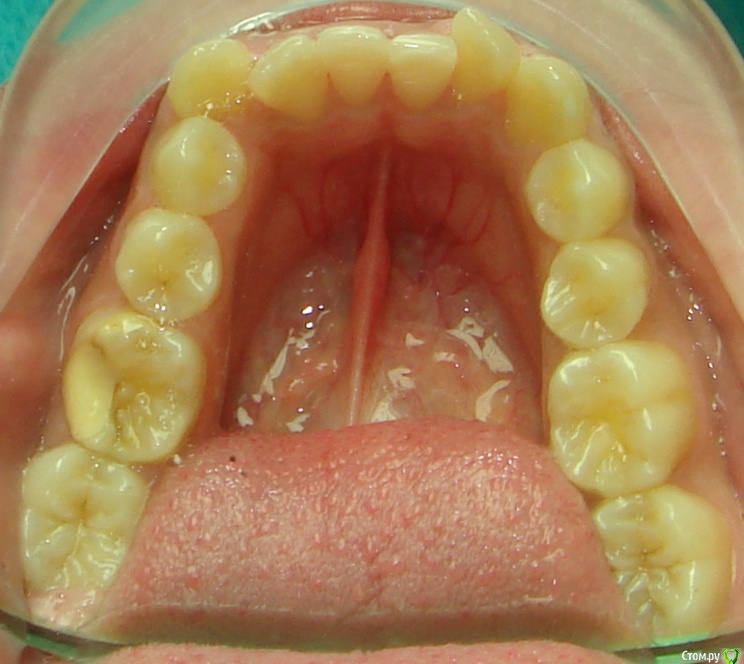

Opdihatop Опубликовано 20 февраля, 2017 Поделиться Опубликовано 20 февраля, 2017 Здравствуйте, коллеги! Вот такой вот случай третьего класса, вертикального роста, множественной первичной адентии и преинтереснейшего 13-го зуба. Девочке 14 лет. Сразу скажу, что вопреки некоторым классикам удалять клык или премоляры мы не будем, будем ставить в дугу, причем на его законное место. Может у кого-то были подобные случаи, поделитесь опытом, будьте добры. Какой план лечения и какая биомеханика тут будут самыми оптимальными? Заранее всем спасибо! Ссылка на комментарий

Opdihatop Опубликовано 20 февраля, 2017 Автор Поделиться Опубликовано 20 февраля, 2017 52, 53 молочные. 12, 22 - адентия. Клык пойдет на место 13. Когда-то на курсе Рафаэля Спены видел подобное, но, к сожалению не зафиксировал на фото. В общем и целом принцип помню. Но тут есть одно огромное НО... 14, 15 началась резорбция верхушек из-за 13 зуба, что видно по КТ. Ссылка на комментарий